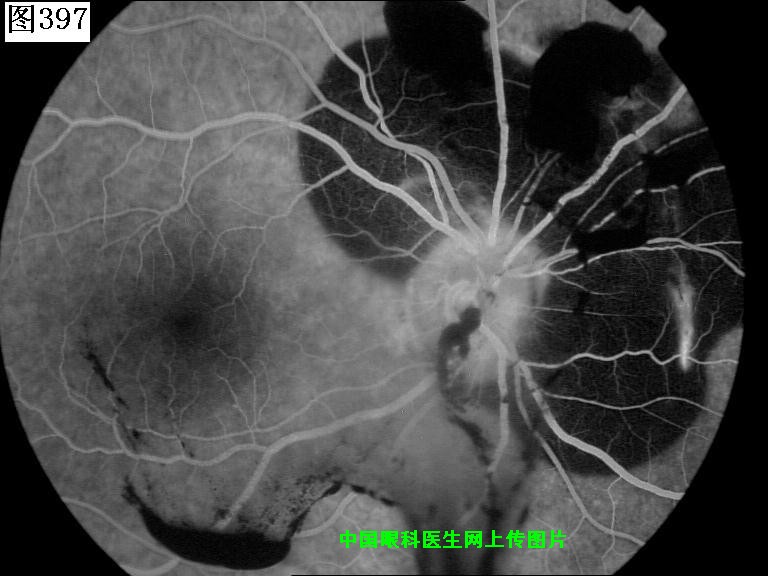

397 398 399 400